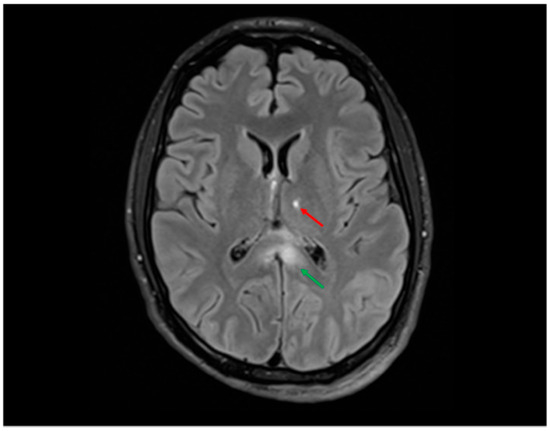

5.3.1. Radiological Findings in Adult DAI

- Grade 1 refers to TAI located in the hemispheres or cerebellum, representing the least severe injury category;

- Grade 2 corresponds to TAI located in the corpus callosum;

- Grade 3 encompasses unilateral TAI in the thalamus or brainstem and bilateral TAI in the basal ganglia;

- Grade 4 includes bilateral TAI in the mesencephalon or thalami, also correlating with worse prognosis;

- Grade 5 denotes bilateral TAI in the pons, identified as the most severe and strongly predictive of poor outcomes.

- Abu Hamdeh, S.; Marklund, N.; Lannsjö, M.; Howells, T.; Raininko, R.; Wikström, J.; Enblad, P. Extended anatomical grading in diffuse axonal injury using MRI: Hemorrhagic lesions in the substantia nigra and mesencephalic tegmentum indicate poor long-term outcome. J. Neurotrauma 2017, 34, 341–352. [Google Scholar] [CrossRef]

- Moen, K.G.; Flusund, A.M.H.; Moe, H.K.; Andelic, N.; Skandsen, T.; Håberg, A.; Kvistad, K.A.; Olsen, Ø.; Saksvoll, E.H.; Abel-Grüner, S.; et al. The prognostic importance of traumatic axonal injury on early MRI: The Trondheim TAI-MRI grading and quantitative models. Eur. Radiol. 2024, 34, 8015–8029. [Google Scholar] [CrossRef]